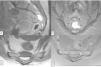

Los tumores benignos de células notocordales (TBCN) son lesiones con diferenciación notocordal que afectan al esqueleto axial. Se caracterizan por cursar asintomáticos o con sintomatología inespecífica, y por pasar desapercibidos radiológicamente por su pequeño tamaño, o bien por ser confundidos con otras lesiones óseas benignas, como hemangiomas vertebrales. Cuando son grandes o sintomáticos pueden plantear el diagnóstico diferencial con metástasis, tumores óseos primarios y cordomas. Presentamos el caso de un TBCN de difícil diagnóstico, en una mujer de 50 años de edad, con una lesión sacra vista en la resonancia magnética (RM). Se programó una biopsia guiada por tomografía computarizada (TC) para filiar la lesión, pero la tumoración no era claramente identificable en la TC, por lo que se utilizaron las referencias anatómicas de la RM para seleccionar el plano adecuado. Tanto la planificación del abordaje como la correlación radiopatológica fueron determinantes para llegar al diagnóstico definitivo.

Benign notochordal cell tumors (TBCN) are lesions with notochordal differentiation which affect the axial skeleton. They are characterized by asymptomatic or non-specific symptomatology and are radiologically unnoticed because of their small size, or because they are mistaken with other benign bone lesions, such as vertebral hemangiomas. When they are large, or symptomatic, can be differential diagnosis with metastases, primary bone tumors and chordomas. We present a case of a TBCN in a 50-year-old woman, with a sacral lesion seen in MRI. A CT-guided biopsy was scheduled to analyze the lesion, finding that the tumor was not clearly recognizable on CT, so the anatomical references of MRI were used to select the appropriate plane. The planning of the approach and the radio-pathological correlation were determinant to reach the definitive diagnosis.